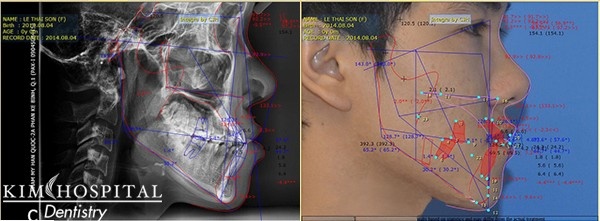

Ca chỉnh nha niềng răng chỉ phát huy được tác dụng khi bác sĩ chẩn đoán đúng nguyên nhân hô, vẩu do đâu. Tại KIM Hospital -bệnh viện thẩm mỹ hàn quốc, mọi ca chỉnh nha đều mang lại kết quả như mong đợi nhờ máy chụp phim kỹ thuật số X-quang ConeBeam CT 3D giúp phân tích cấu trúc xương hàm chi tiết.

Bằng phần mềm Vceph 3D của Mỹ, bác sỹ có thể đưa ra kế hoạch điều trị chi tiết với sự di chuyển của từng răng hàm trên, thời gian di chuyển bao lâu và kết quả của việc niềng răng như thế nào bằng 3D. Đây cũng là một trong những yếu tố khác biệt khi thực hiện chỉnh nha tại một bệnh viện thẩm mỹ.

| Phần mềm phân tích niềng răng hô Vceph đưa ra kết quả niềng răng trước khi bước vào giai đoạn gắn mắc cài hoặc invisalign. |